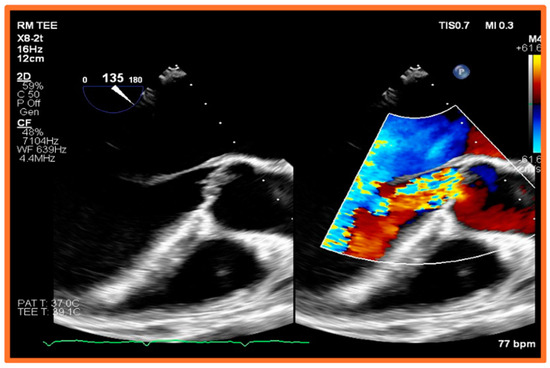

5.2. Transesophageal Echocardiography (TEE)